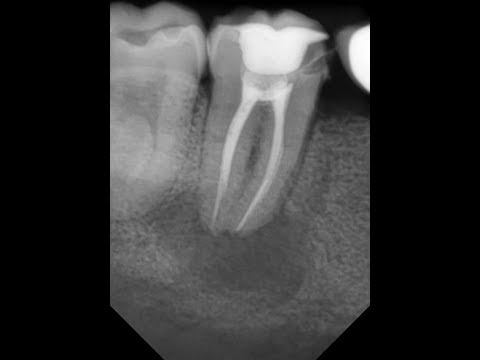

Эндодонтический материал «Белодез-Активатор» производства ВЛАДМИВЫ понижает коэффициент поверхностного натяжения жидкостей для химического расширения и жидкостей для антисептической обработки корневых каналов зубов, увеличивает смачивающую способность ирригантов, обеспечивает их проникновение в труднодоступные участки системы корневых каналов и в дентинные канальцы, образует пену для лучшего удаления дентинных опилок и органических остатков из системы корневых каналов. «Белодез-Активатор» образует прозрачный раствор в сочетании с эндодонтическими ирригантами, содержащими гипохлорит натрия («Белодез»), ЭДТА («ЭндоЖи №2») или хлоргексидина биглюконат («Белсол №2»).